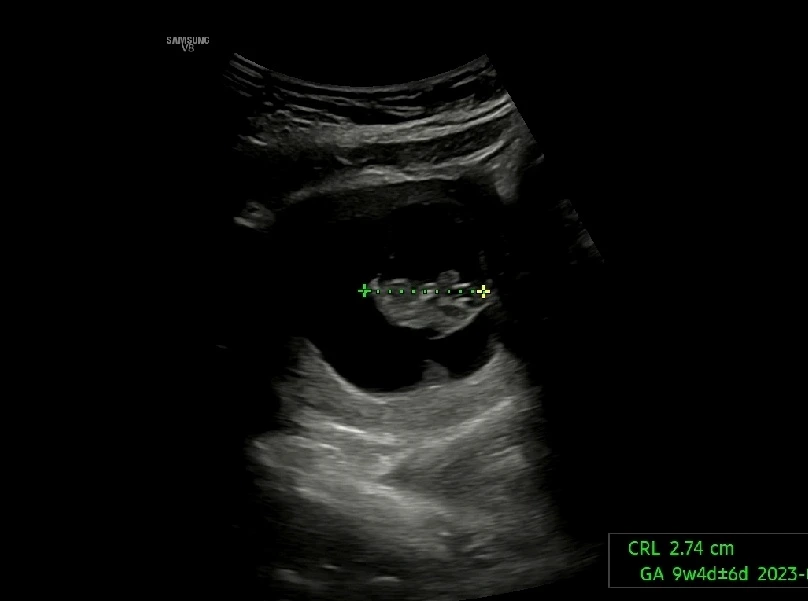

임신 9주차 초음파 (2023. 2. 11)

9주차에도 사이좋게 남편이랑 초음파를 보고 왔다! 초음파 속 사진이 뭐가 무엇인지 정확하게 잘은 모르지만 (ㅎㅎㅎ) 그저 신기해.

임신9주차 초음파